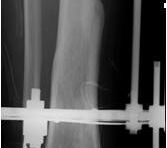

• Primäre oder posttraumatische Arthrose des OSG und USG (Abbildung 1, Abbildung 2).

• Revision einer gescheiterten Fusion des OSG/ USG (Abbildung 3, Abbildung 4).